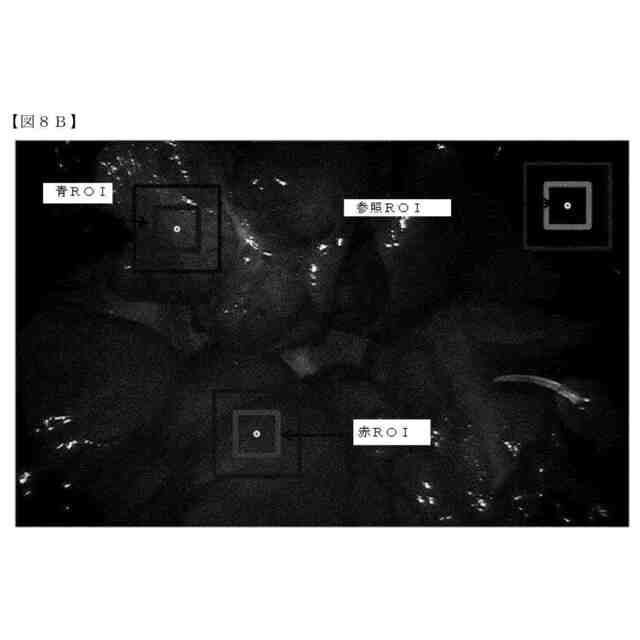

第一の実施形態では、本開示は、従って、対象の解剖学的構造の、例えば、外科手術等の医療処置中の自動灌流評価のためのシステムに関する。システムは、対象の血中への所定量の蛍光造影剤の注入を制御するように構成され得る。注入は、システムの制御下にあることができる、制御可能な注入ポンプによって行うことができる。注入ポンプは、システムの一部であってよく、システムは、少なくとも1つの蛍光造影剤を保持するための少なくとも1つの制御可能な注入ポンプを含む。すなわち、この注入ポンプは、所定量の当該蛍光造影剤を対象の血中に注入するように構成され得る。好ましくは、システムは、所定量の当該蛍光造影剤が一定間隔及び/または所定の間隔で繰り返し注入されるように構成される。システムはさらに、蛍光造影剤の注入後の当該解剖学的構造の組織の時系列の蛍光画像、別名、映像を受信及び分析するように構成され得る。この分析に基づいて、当該解剖学的構造の少なくとも1つの灌流パラメータを特定することができる。

本開示のシステムは、それ故、さらに、蛍光造影剤の最初の少量のボーラスを注入するように注入ポンプを制御し、その後、この最初のボーラスから生じる蛍光発光を分析するように構成され得る。この最初の少量のボーラスは、好ましくは、生理食塩水でのフラッシングと組み合わせ、状況、すなわち、使用される蛍光剤のタイプ、及び患者の形態、例えば、年齢、体重、身長等に応じて選択する必要がある。しかしながら、対象の体重の0.01mg/kg未満の量、すなわち、50kgの患者に対しては0,5mg未満及び100kgの患者に対しては1mg未満が、特に、ICGが使用される場合に通常望ましい開始点である。

本発明者らは、解剖学的構造の組織からの定量化可能な蛍光発光が、例えば、コンピュータ画像分析を使用することによって、人間の目に見える蛍光発光よりもはるかに小さいことに気付いた。すなわち、蛍光信号強度は、外科医による目視検査によってではなく、コンピュータによる画像認識及び画像分析によって測定可能な大きさが必要なだけであるため、はるかに少ない用量、例えば、マイクロドーズが可能である。すなわち、マイクロドーズの蛍光剤を対象に投与することができ、例えば、灌流パラメータをそれから特定することができる。